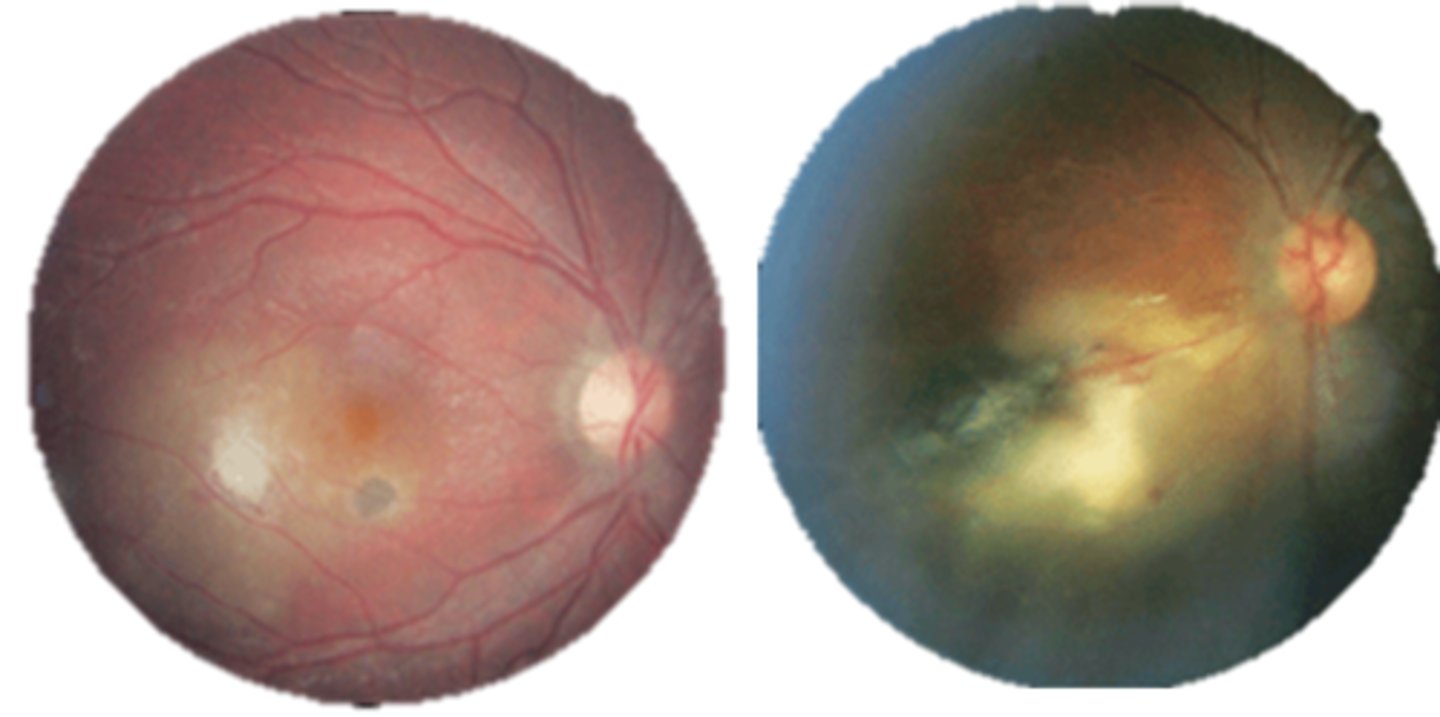

What finding of toxoplasmosis is seen in A/B?

retinitis turns into hazy scar with nerve pallor

What finding of toxoplasmosis is seen in C/D?

scarring overtime with VA loss/scotoma